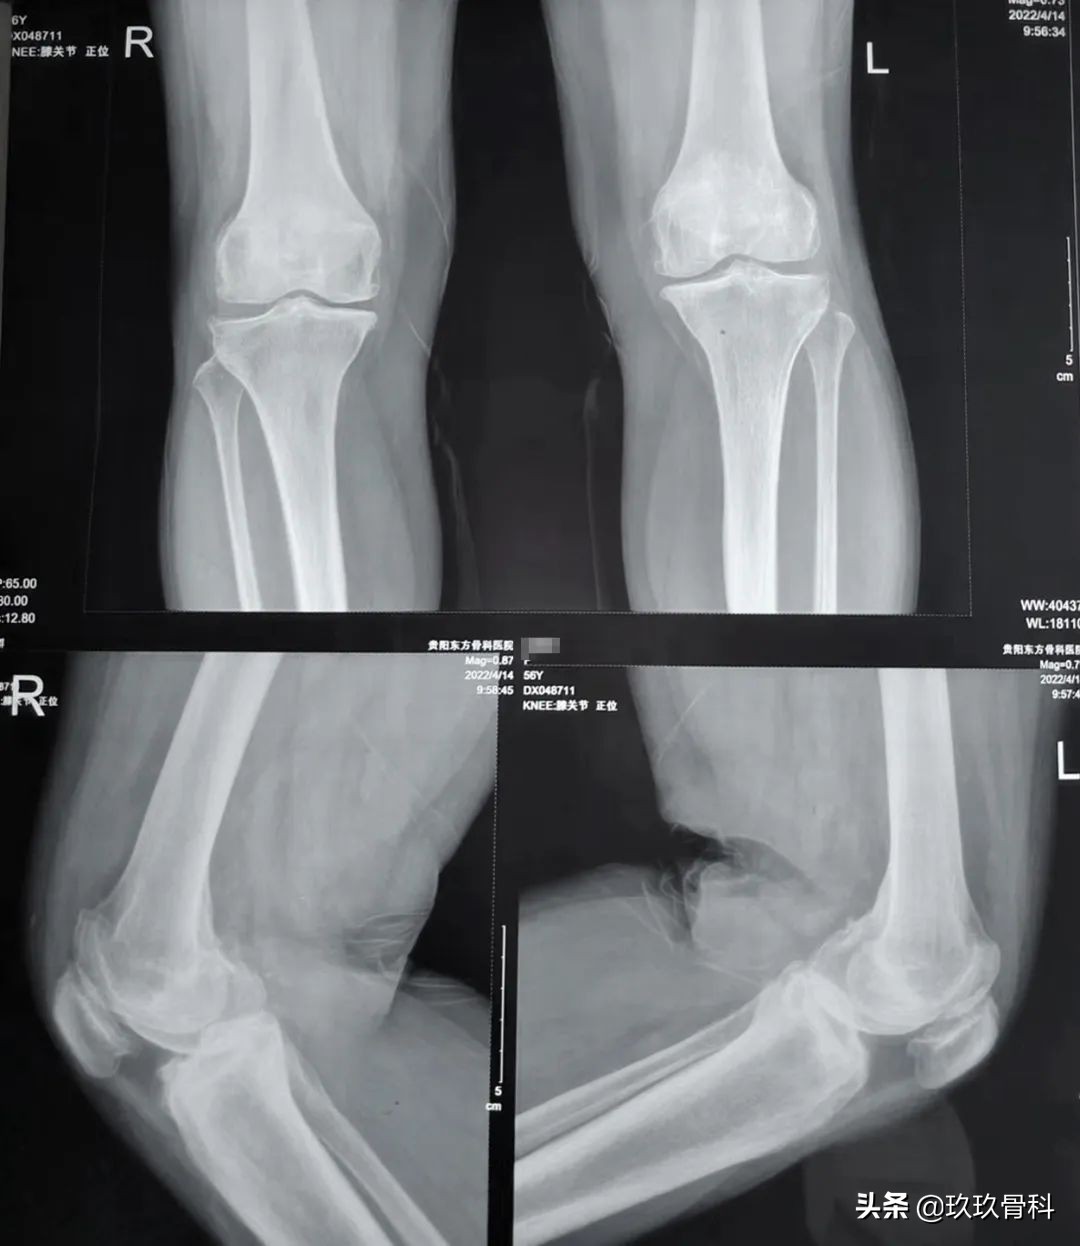

双膝关节未见明显畸形、肿胀,双膝皮温不高、皮色不红,双膝髌骨内侧压痛明显,以关节线处压痛为甚,以右膝疼痛明显,双膝关节功能活动稍受限,左膝活动度(伸约5°,屈100°),右膝活动度(伸约5°,屈约90°),双膝关节活动时未扪及明显摩擦感及弹响,髌股关节活动欠佳,双膝磨髌实验、麦氏试验、研磨试验均为(+),内外侧应力试验、抽屉试验(-),生理反射存在,病理征阴性,双下肢肌力、肌张力正常,余无明显阳性体征。

双膝关节正侧位片结果示:双膝关节退行性骨关节炎。

术前影像